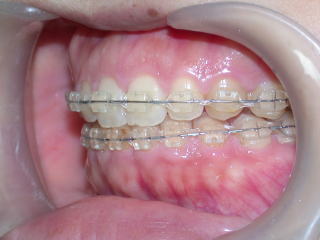

術後を予測するセットアップモデル。